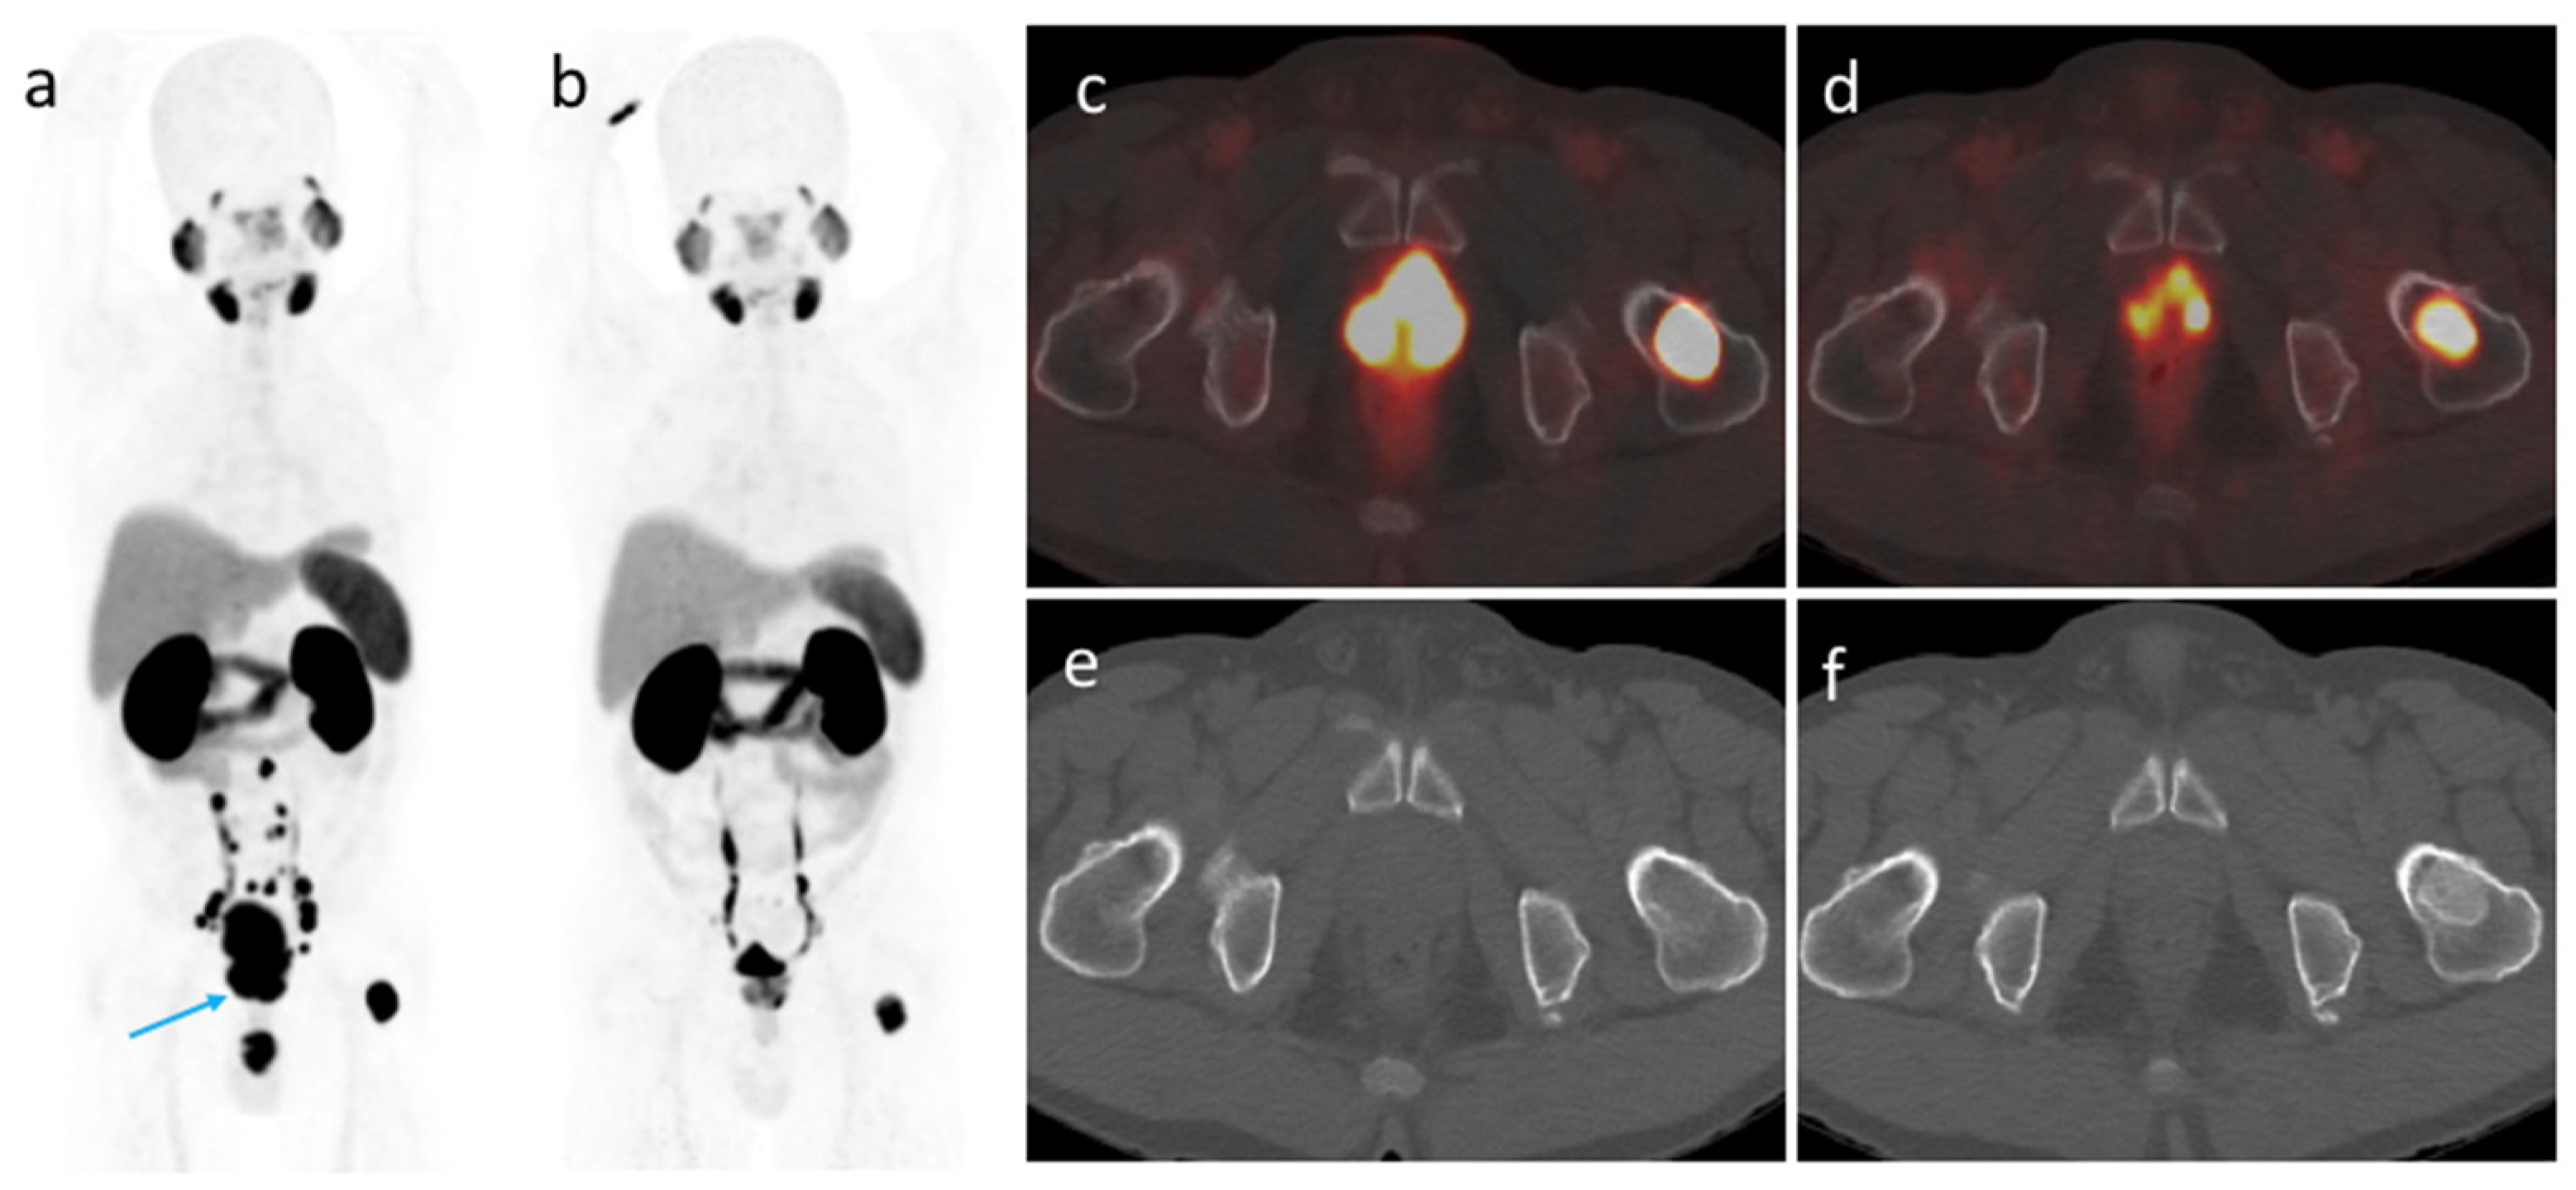

3.4. [68Ga]Ga-PSMA-11 PET/CT Imaging after ADT

3.5. Changes in [68Ga]Ga-PSMA-11 PET/CT Indices According to The ISUP Grade Groups and ADT Schemes